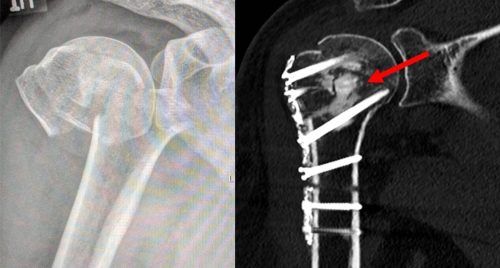

München – Chirurgie kann Puzzlearbeit sein. Zum Beispiel, wenn wegen Osteoporose ein Knochen vielfach gebrochen ist, wie Sie es auf dem linken Bild oben sehen, Es zeigt die zerborstene Schulter einer älteren Dame, die beim Gassigehen gestürzt ist. Auf der rechten Seite sieht man das Bild derselben S